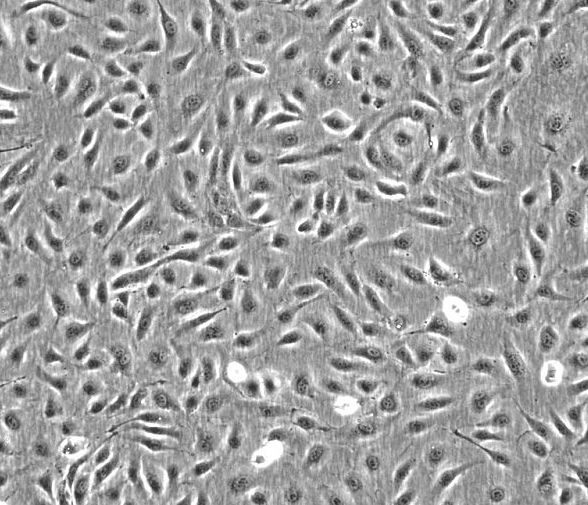

- 细胞形态:

淋巴母细胞样

形态:淋巴母细胞

背景资料:1967年,该细胞系Klein E和Klein G建系,源于一名16岁患有Burkitt淋巴瘤的黑人男性,beta-2-微球蛋白阴性,表达EBNA, VCA,sIg。该细胞携带EB病毒,是一个典型的B淋巴母细胞系,可用于白血病发病机制的研究。